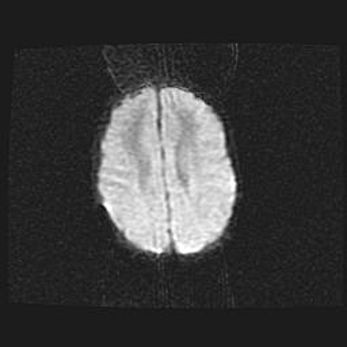

Сообщающаяся гидроцефалия. Кистозная энцефаломаляция головного мозга.

Возраст: 3 месяца 4 дня

Вес: 3100 г

Пол: женский

Окружность головы: 34 см

Срок гестации: 31 неделя

Кистозная энцефаломаляция головного мозга - одна из форм поражения головного мозга в детском возрасте. Характеризуется возникновением множественных и распространённых кист в коре, белом веществе и подкорковых образованиях головного мозга у плодов, новорождённых и детей раннего возраста. Развитие кистозной энцефаломаляции связано с внутриутробной асфиксией и гипотонией, родовой травмой, тромбозом синусов, пороками развития сосудов, инфекциями, сепсисом и другими причинами. Наиболее значимые инфекционные агенты: вирусы простого герпеса, цитомегалии, краснухи, токсоплазмы, энтеробактерии, золотистый стафилококк и другие.